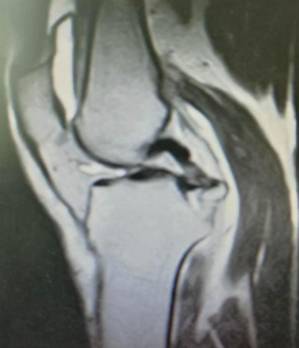

手术技术上与国内领先医院接轨,并不断创新。系统开展膝关节骨性关节炎的阶梯治疗方案,早期采用中医中药、理疗、肌力训练等方法;中期采用膝关节周围截骨、单髁置换等手术治疗,充分保留膝关节功能,术后患者康复快。终末期采用膝关节表面置换术治疗。系统开展股骨头无菌性坏死的保头治疗,早期可采用中医中药内服,钻孔减压术治疗,中期可采用髋关节外科脱位技术,充分刮除头内坏死骨,植入新鲜骨质,使坏死股骨头重新获得新生。常规开展复杂的人工髋膝关节置换手术、人工髋膝关节翻修手术。术后采用先进的康复理念和康复方案帮助患者在无痛状态下恢复关节功能。

胫骨高位截骨治疗膝关节骨关节炎

优点:创伤小,疗效确切,适合生活方式活跃的年轻患者。